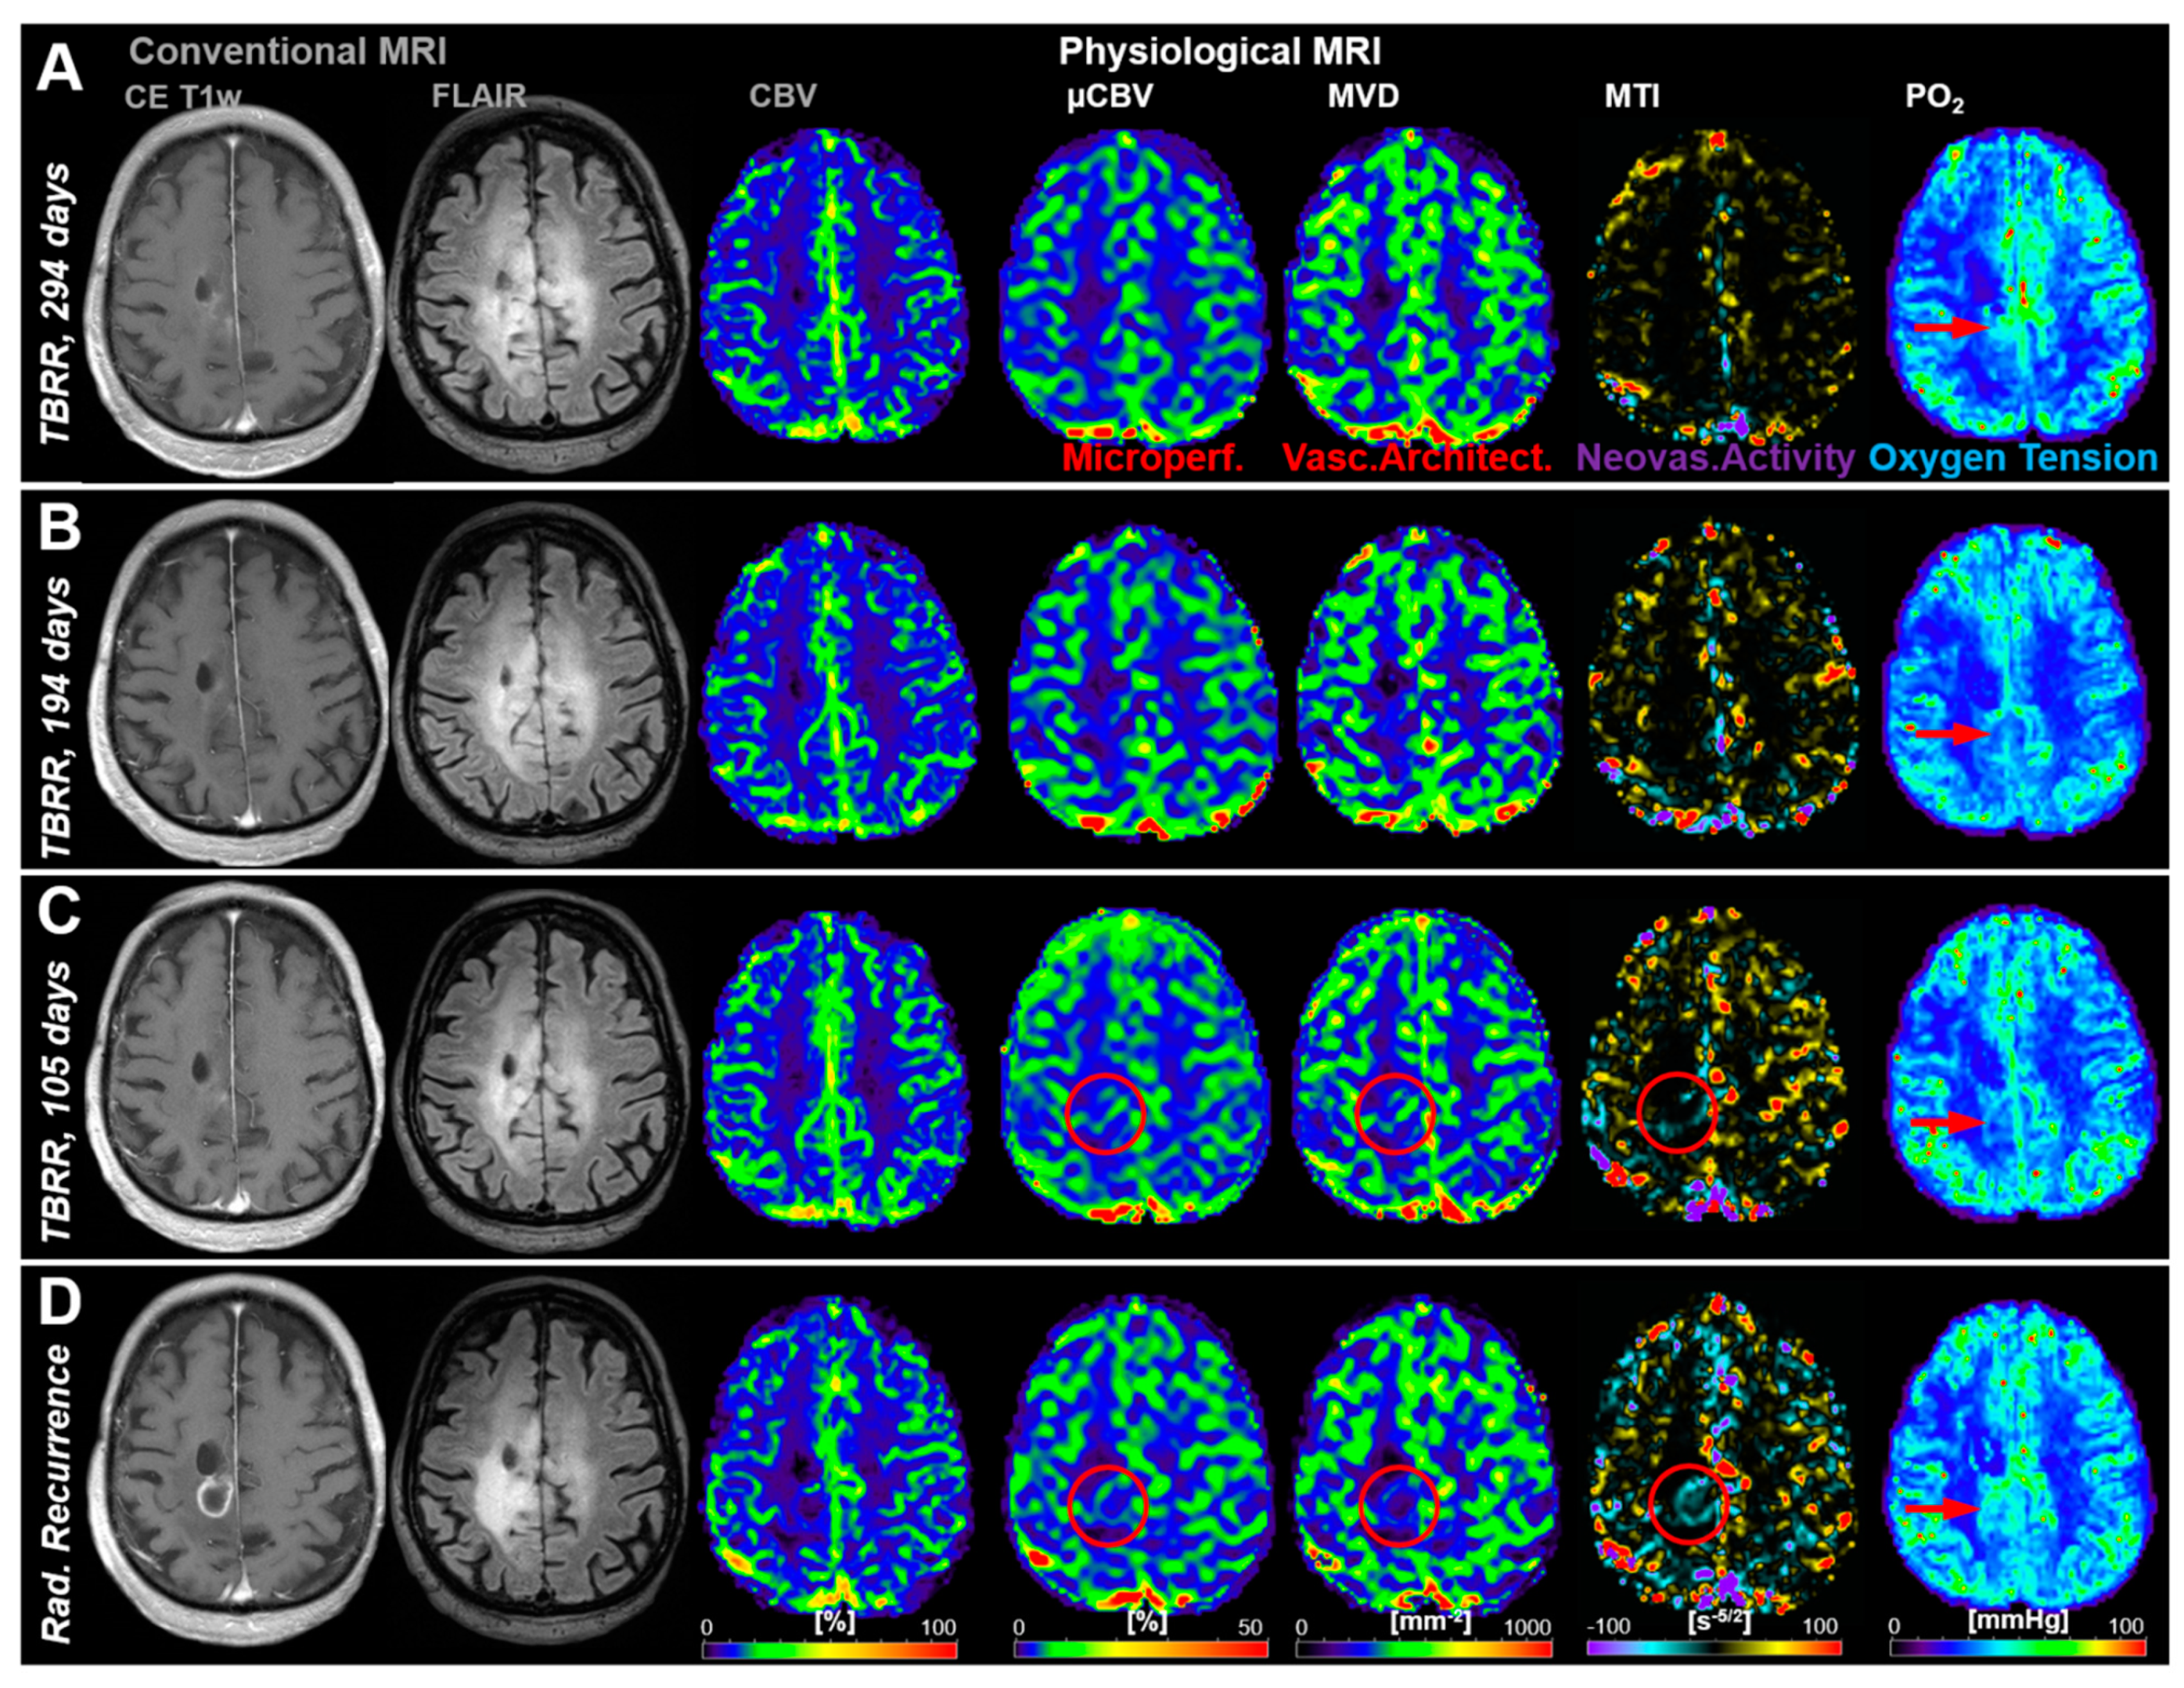

3.2. Follow-Up Examinations with Conventional and Physiological MRI

3.3. Time Courses of MRI Biomarker Changes Preceding Radiological AG Recurrence